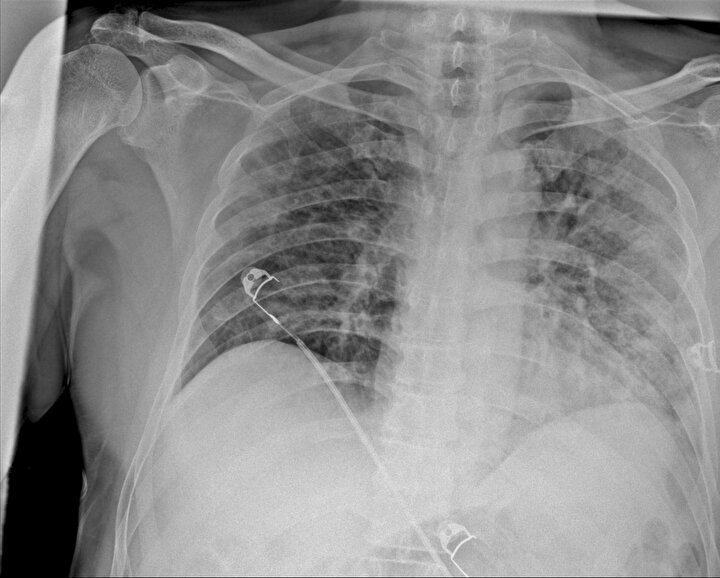

Ankara Şehir Hastanesinde koronavirüs tedavisi gören hastalara ait akciğer görüntüleri incelendi. Görüntülerde, hastalığın ne kadar hızlı ilerlediği ve akciğerleri nasıl tuttuğu ortaya çıktı.

Prof. Dr. Karalezli, koronavirüs tedavisi gören hastalara ait akciğer görüntülerinden hastalığın yol açtığı tahribatı ve hastalar üzerindeki etkileri anlattı.

Normal akciğer görüntüleri ile koronavirüs hastalarının akciğer görüntüleri arasında ciddi farklar bulunduğunu belirten Karalezli, şu bilgileri verdi:

"İnsanların aradaki farkları anlamaları için her iki akciğer görüntülerine de yer verdim. Görüntülerdeki beyazlıklar akciğerdeki tutulumu gösteren görüntüler ne yazık ki. Bu hastalar yoğun bakım hastaları. Filmler birbirine az çok benzeyen şekilde. Altta yatan hastalığı olanlarda ise daha kötü seyrediyor."